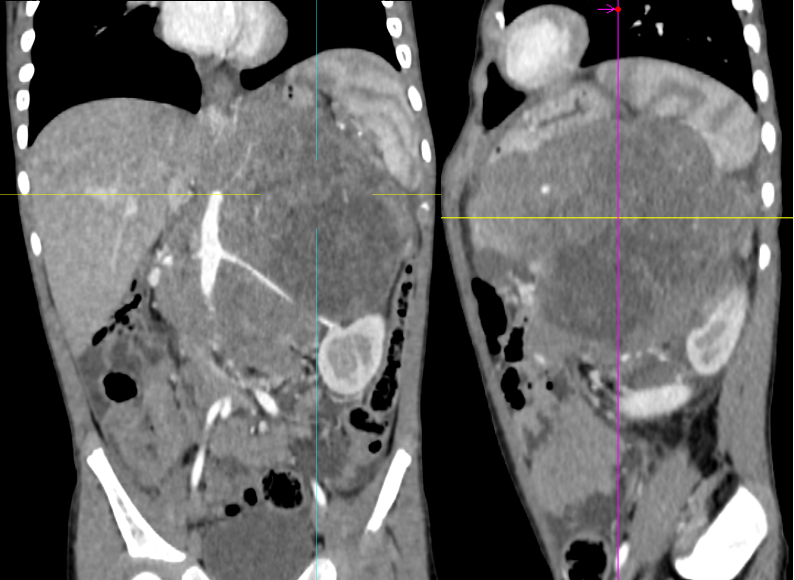

病例三

男,3 岁,因「间断腹痛 1 周,发现腹腔肿物 1 天入院」。

影像描述:左上腹部见巨大团状异常密度影,最大层面大小约 11.9×9.2×13.8 cm,病变内密度不均,见不规则形低密度区,左侧肾上腺显示不清,病变与左肾、胰腺体尾部分界不清,病变跨越中线,包绕腹主动脉、腹腔干、脾动脉、肝总动脉、肠系膜上动脉、左肾动、静脉,门静脉主干及其属支呈受压改变。